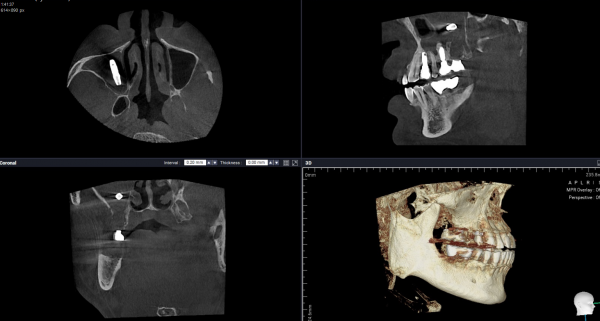

먼저 3D CT로 임플란트 위치, 상악동 점막 비후, 잔존골 높이, 상악동막 상태, 주변 구조물과의 관계를 확인해야 합니다. 필요하면 구강스캐너와 교합 분석까지 더해 재치료 방향을 세워야 합니다. 이 과정이 정교해야 무리한 재수술을 줄일 수 있습니다. 상악동 전위 케이스에서 CBCT 기반 평가가 중요하다는 점은 여러 문헌에서 일관되게 언급됩니다.